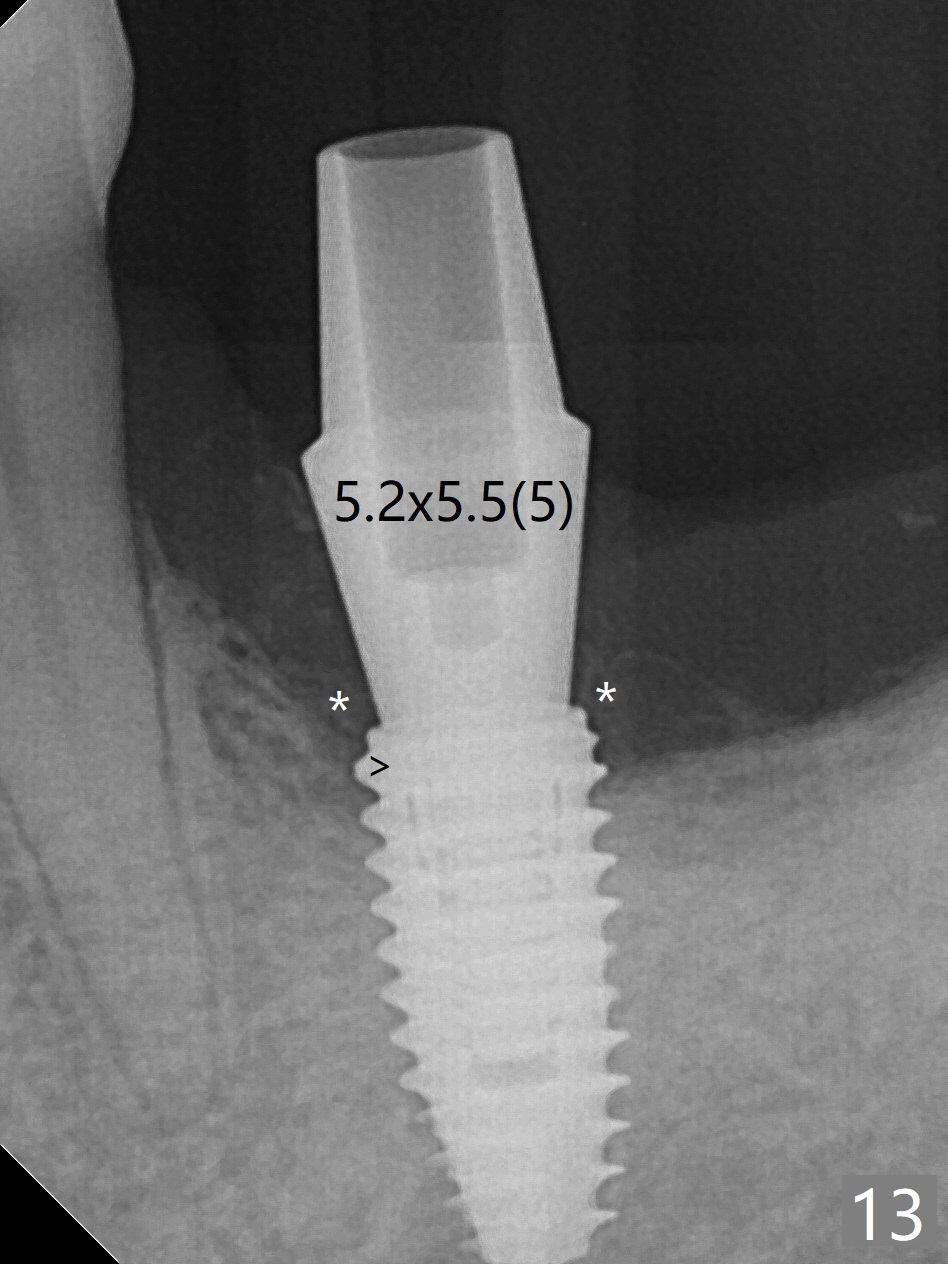

When the patient returns for #19 extraction (Fig.1), there is no 5x10 mm implant available. In fact the smaller one (4.5x10 mm) is able to achieve insertion torque >60 Ncm with more room for autogenous bone/allograft horizontally (Fig.2 *). After insertion of a definitive abutment (6.5x5.5(4) mm), more allograft is placed coronally (Fig.3 *). The gingiva that was between the mesial and distal roots before extraction (Fig.1 *) is transferred distal (Fig.4.5 *). An immediate provisional (Fig.6 P) is fabricated to close the socket opening, followed by periodontal dressing (data not shown). The latter is partially detached 2 weeks postop (Fig.7 D). When it is removed, some of possibly collagen plug is exposed distobuccally (Fig.8). When the plug is removed, some of the bone graft (Fig.9 *) is exposed distal to the provisional (P). New periodontal dressing is applied to keep the exposed graft in place. There is no apparent thread exposure 4 months postop (Fig.10). The abutment is loose 4 months post cementation, probably related to unfavorable crown/implant ratio; but when the abutment is retightened, there is a gap between it and the implant (Fig. 11 >). After relieving the proximal contact of the crown, the abutment is retightened one more time with the same gap (Fig.12 >). In fact the latter is present previously. A narrower abutment with longer cuff appears to be completely seated, probably avoiding contact with the regenerated crestal bone (Fig.13 *). If the new crown gets loose, bury a driver inside the abutment.